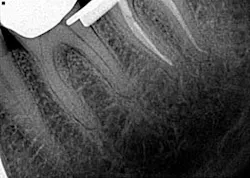

• Missed canals

Know your tooth anatomy and the possible variations of the canals (figure 2). The molars present with the most diverse canal composition—“additional canals in the mesial roots of maxillary molars and the distal roots of mandibular molars are the most frequently missed” (2)—but even the premolars and incisors can prove to be a formidable foe. Remember the article by David Landwehr, DDS, MS, titled “The myth of ‘easy’ root canals in endodontics”? Read it if you haven’t. Lastly, don’t skimp on your occlusal access and use magnification.